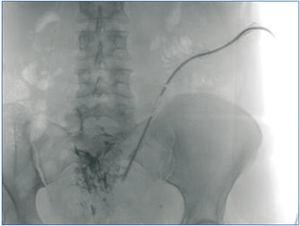

Caso 2. Mujer de 65 años que inicia DP después de un segundo trasplante. Durante la cirugía para colocación del catéter, se realizó liberación de múltiples adherencias intestinales. Desde el inicio, la infusión se hacía sin problemas, pero el drenaje era imposible. Se realizó cateterografía que confirmó la sospecha de atrapamiento; posteriormente, pudo comprobarse en la cirugía de retirada del catéter (figura 2).

Figura 2. Caso 2